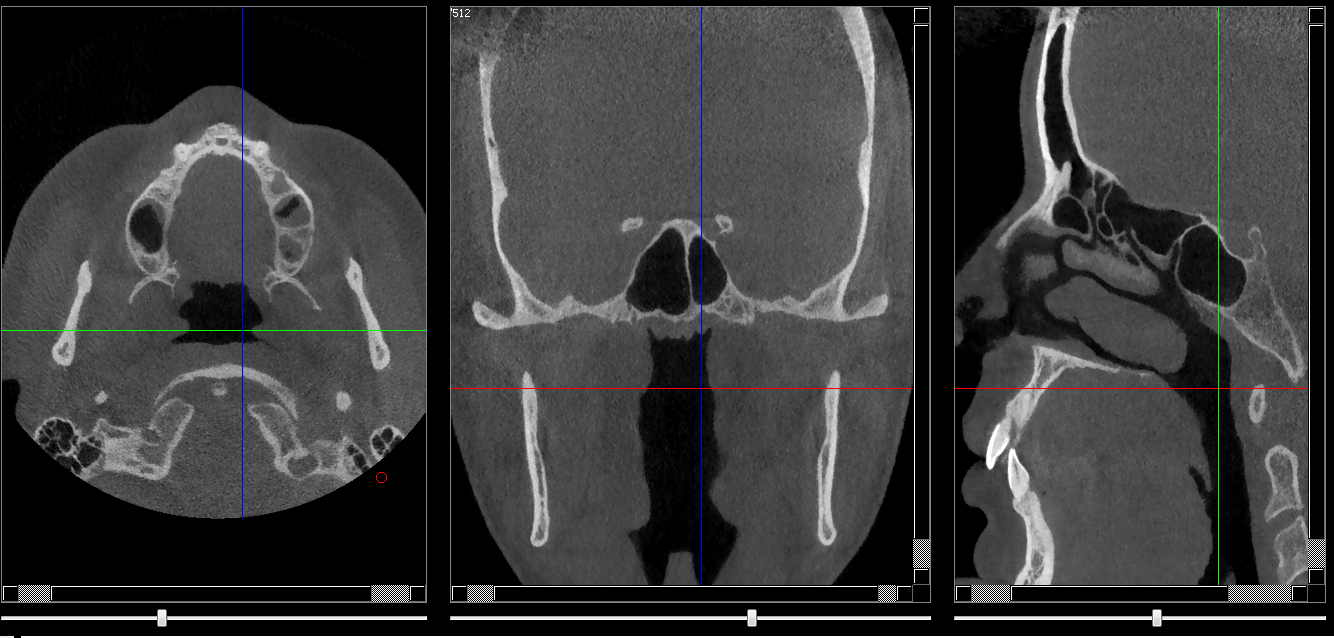

Structures osseuses

Repères anatomiques

- Coupe transversale

- Début : Rhinopharynx

- Fin : clivus

- Coupe frontale

- Début : Partie post du palais dur

- Coupe saggitale

- Début : Processus clinoide droit

- Fin : Processus clinoide gauche

Infos sur l'image

- Auteur : Pr Bourzgui

- Co-auteur : Dr Makoure

- Affiliation : Orthopédie dento-faciale

- Date production : 2019